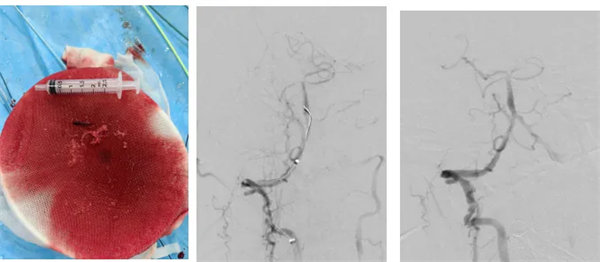

術中,介入團隊精準定位血管閉塞部位,通過微導絲“探路”聯合球囊擴張技術開通右側椎動脈開口,造影椎開口殘余狹窄60%?;讋用}血栓形成,基底動脈管腔狹窄55%,基底動脈尖堵塞,右側大腦后動脈及小腦上動脈未見顯影,左側大腦后動脈P3以遠閉塞。

席聰準確鎖定患者基底動脈處血栓,采用抽吸取栓技術快速開通血管,成功取出堵塞部位2cm的血栓。再次造影示:右側大腦后及雙側小腦上動脈再通,右側大腦后動脈P3段以遠閉塞,考慮慢性閉塞,推注替羅非班,血流明顯加快。隨后采用支架植入術開通右側椎動脈開口處,術中影像顯示:支架貼壁良好,無明顯殘余狹窄,顱內血管顯影良好。